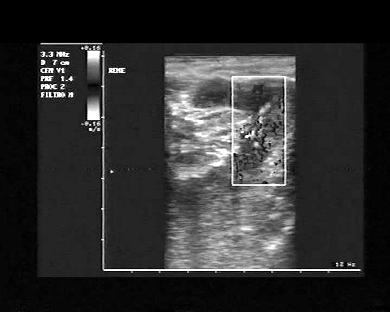

Data inserimento: 17/09/2008

Ecografie del: 09/09/2008

Strumento: Esaote MyLab 25

Età paziente: M 41 anni

Le immagini ed il video documentano al rene sinistro immagine iperecogena, con con d'ombra posteriore, riconducibile a litiasi, delle dimensioni di 8 mm. ed ulteriore calcolo in sede ureterale sinistra delle dimensioni di 4-5 mm. iuxta-vescicale. Il paziente durante la notte ha presentato sintomatologia tipica per colica renale sinistra. Le immagini ed il video presentati rendono ragione della sintomatologia del paziente.

Presentazione: Dr. Massimo Dolciotti - Ancona

Elaborazione digitale: Andrea Dini - Ancona

VISUALIZZA IL VIDEO